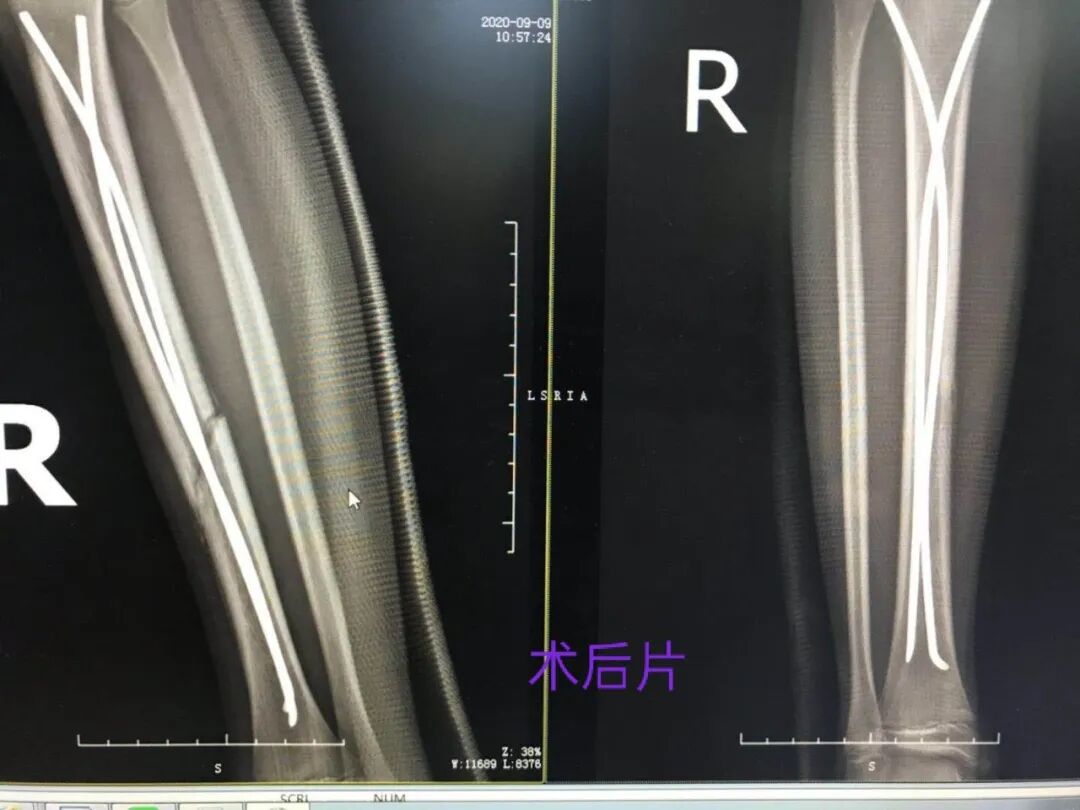

很快,吴东明主任及其团队为患者施行了手术,闭合复位、经皮打孔、钛金弹性髓内钉置入固定,在骨三科团队的协同配合下,手术一气呵成,过程十分顺利。

术后患儿疼痛较小,愈合较快,2周后复查DR片,见骨折端对位对线良好,且可见骨痂形成,这是钢板螺钉内固定所无法达到的,因为放置钢板的过程剥离骨膜,易导致骨折端愈合延迟。